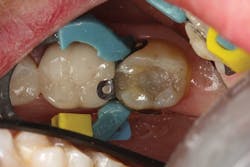

However, as mentioned earlier, getting the composite adapted to both the buccal and lingual cavosurfaces at the same time can be tricky. To address this, I have found it easier to place one increment of resin in a way that covers the entire buccal side of the preparation, including the marginal ridge area (figure 2), and light cure it prior to finishing the fill with the lingual increment. This requires one extra step, but it gives me the peace of mind that I am reducing the polymerization shrinkage on the opposing cavosurfaces as well as eliminating the back and forth nature of trying to adapt the composite to both sides of the cavity preparation (figure 3).